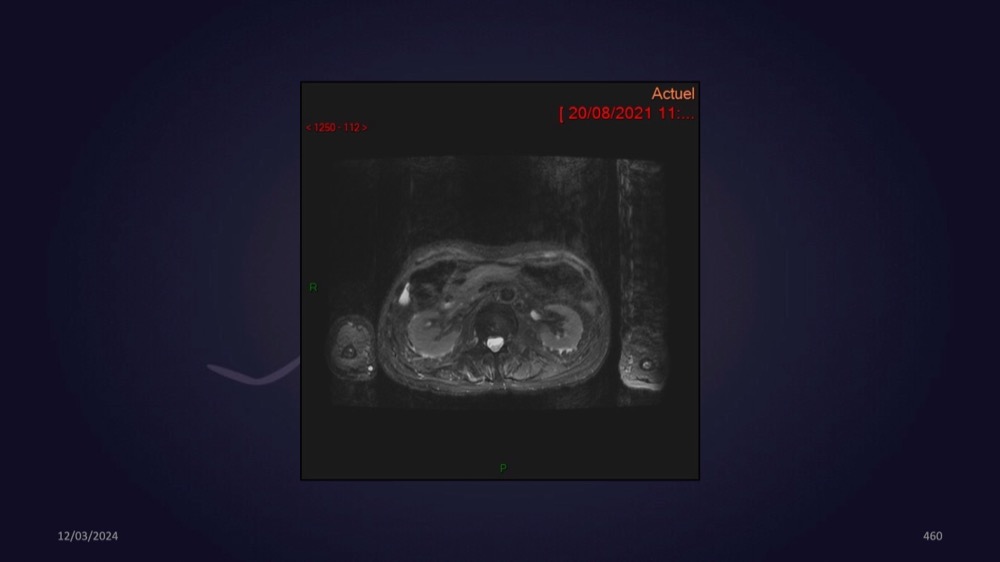

Mezhgani / Dimitri Boulos / Carlier 23/03/2022